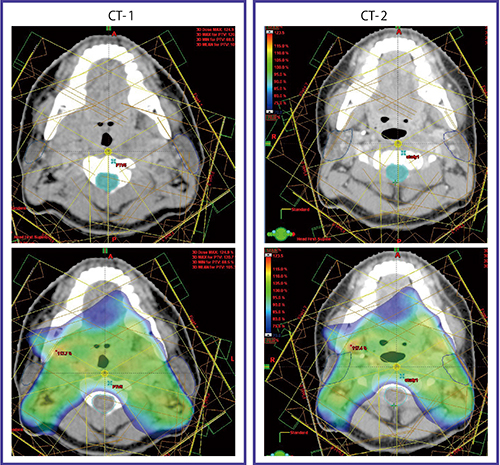

これらの問題点を克服すべく,当院では,咽頭癌に対しては46~50Gy/23~25回の全頸部に対するIMRTの後,原発巣(GTVp)および転移リンパ節(GTVn)には合計70Gy/35回までのブーストIMRTを行うtwo-step法を原則としている3)。そのため,治療開始前CT(CT-1)と,30〜40Gy/15〜20回の時期に2回目のCT(CT-2)を撮影する。

IMRT two-step法の意義を明らかにするために,化学放射線療法で治療した頭頸部癌20例を対象に,CT-1とCT-2におけるGTVおよび耳下腺の体積および位置の変化を検討した4)。その結果,CT-2でのGTVpおよびGTVnの体積は63%および52%縮小し,耳下腺体積も18%縮小していた。耳下腺外縁は,内側に平均4.2mm変位していた。

図3に,上咽頭癌症例のCT-1と初期計画,CT-2と移植計画を示す。CT-2では,頸部リンパ節は縮小し,頸部は明らかに細くなっている。このため耳下腺は内側に変位し,初期計画で治療を続けると耳下腺は高線量域に含まれることとなる。

図3 治療開始前CT-1と38Gy時点のCT-2

CT-2では頸部リンパ節が縮小し,体輪郭も細くなっている。CT-1を基に作成した初期計画をCT-2に移植すると(右下),耳下腺が内側に変位したため高線量域(70% 線量域)に含まれる。